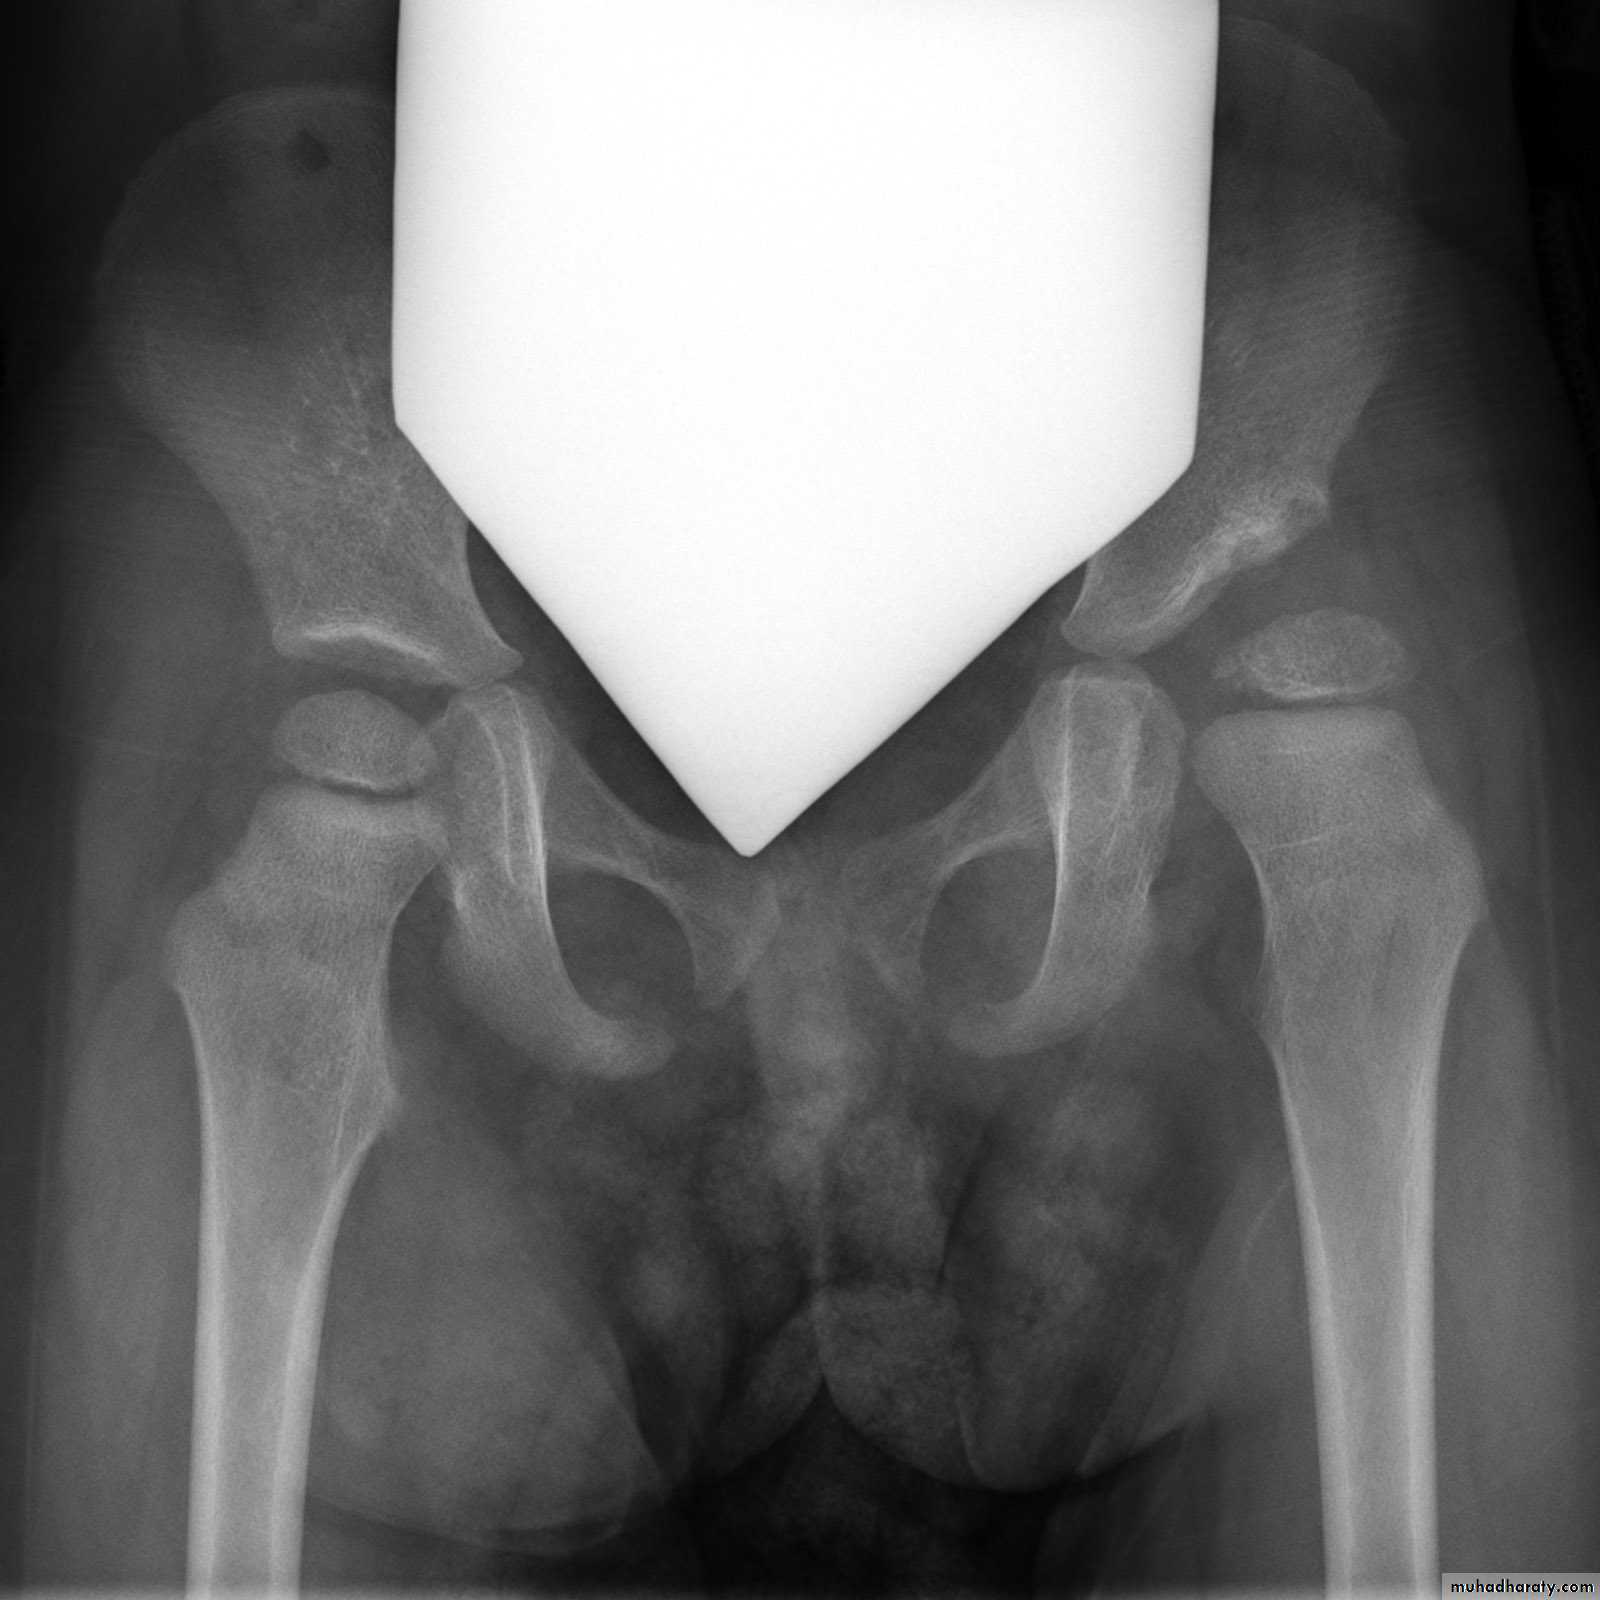

*Triradiate pelvis in which pelvic side walls bend inward (sever cases of osteomalasia )

* Looser's zones these are thin short lucent lines with sclerotic margins running across the cortex at right angle, best seen in the scapula , femoral neck , pubic rami (osteomalacia )